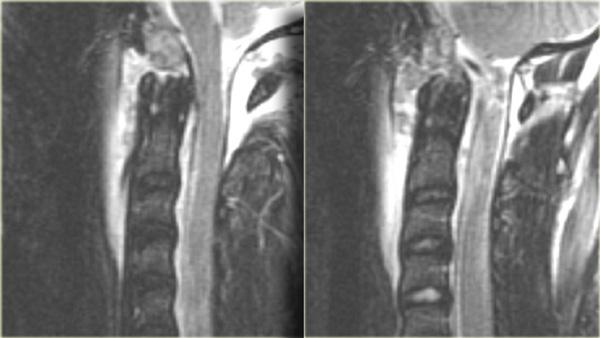

Bong gân tăng gấp (3)

MRI giải thích tình trạng thần kinh của bệnh nhân này.

Các dấu hiệu trên MRI bao gồm:

- Tổn thương mô mềm nặng nề ở các cấu trúc cạnh sống phía sau, đặc biệt tại mức C5-6, nơi dây chằng gian gai và dây chằng vàng bị đứt

- Rách đĩa đệm C5-6 với di lệch ra phía sau C5

- Phù nề tủy sống lan rộng

Tiếp tục với hình ảnh mặt cắt axial.

Hình ảnh axial cho thấy tổn thương tủy sống và ngoài ra còn có sự vắng mặt của khoảng trống dòng chảy (flow void) ở động mạch đốt sống phải.

Điều này gợi ý huyết khối do bóc tách động mạch.

Kết luận, bệnh nhân này không có gãy xương, nhưng có bong gân tăng gấp nặng kèm thoát vị đĩa đệm cấp tính, tổn thương tủy sống không xuất huyết và huyết khối động mạch đốt sống.

Chụp mạch cộng hưởng từ (MRA) xác nhận tắc nghẽn động mạch đốt sống phải.